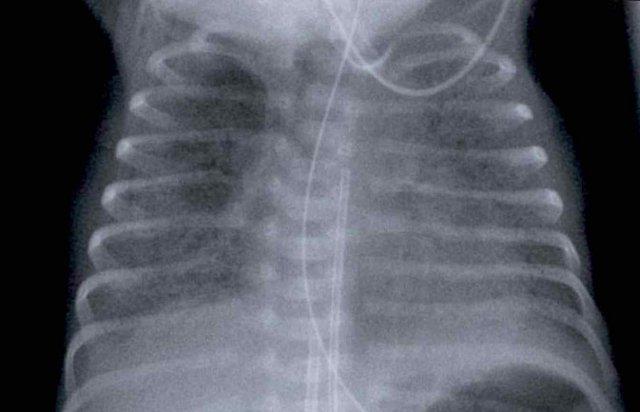

One day old neonate, 29

weeks of gestational age.

Image

- Hyperinflation due to CPAP.

- Granular opacification of

both lungs with air bronchograms. - NG tube in good position.

- Vessels and cardiac

silhouette are harder to distinguish.

Conclusion: RDS grade 2.